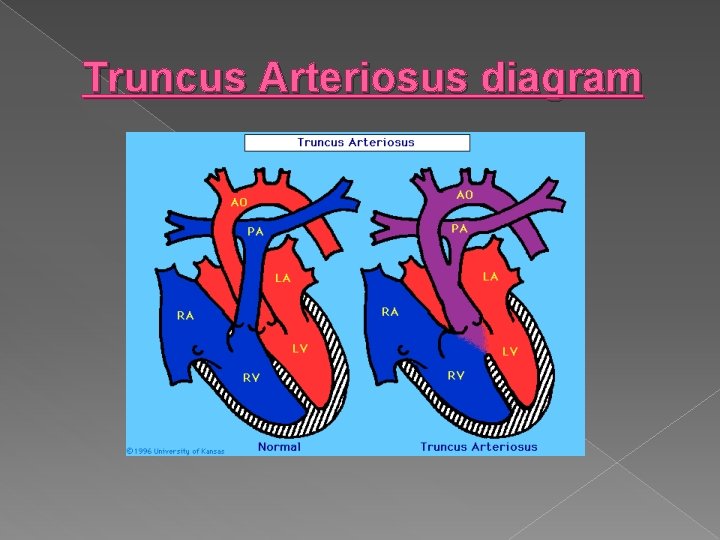

Truncus Arteriosus � A single large vessel arises from the base of the heart. A VSD is usually present, and 48% of fetuses have other noncardiac anomalies.

Truncus Arteriosus diagram